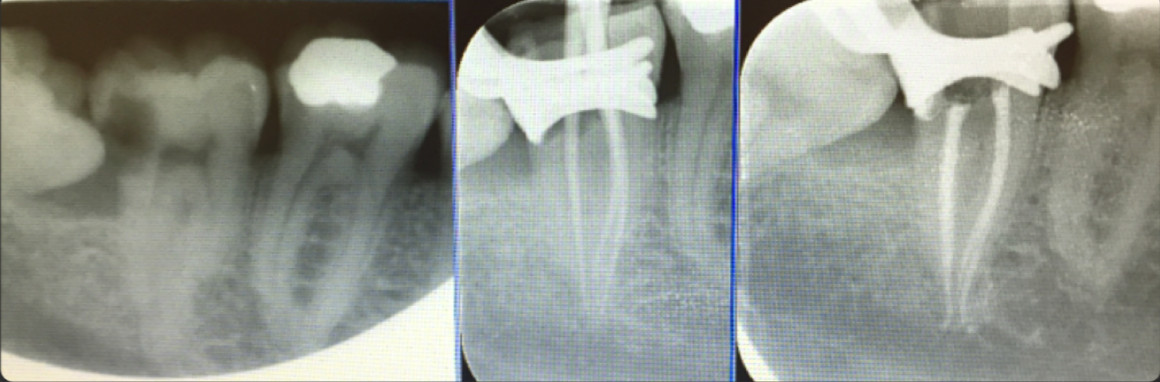

Endodoncia

Realizamos técnicas de endodoncia avanzada, que incluyen endodoncia microscópica, diferentes técnicas rotatorias, obturación termoplástica, revascularización de dientes jóvenes traumatizados y otras técnicas novedosas.